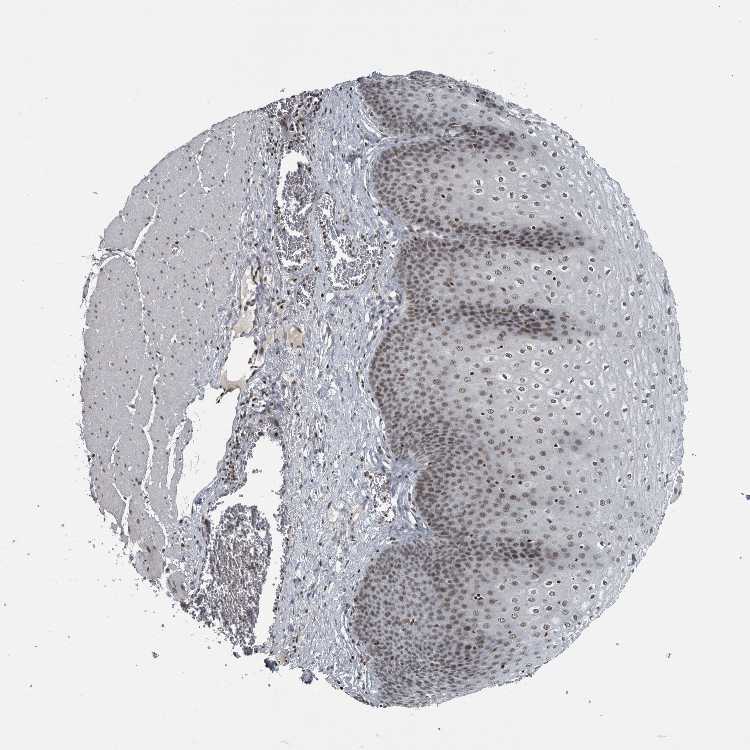

ESOPHAGUS - Antibody stainingi

Antibody staining in the annotated cell types in the current human tissue is reported as not detected, low, medium, or high, based on conventional immunohistochemistry profiling in selected tissues. This score is based on the combination of the staining intensity and fraction of stained cells.

Each image is clickable and will lead to virtual microscopy that enables deeper exploration of all samples and also displays staining intensity scores, fraction scores and subcellular localization as well as patient and tissue information for each sample.

Antibody HPA027009

Squamous epithelial cells Medium